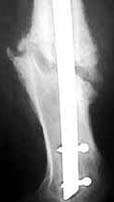

Seeking advice on further management of 26 years old male with femoral nonunion. He sustained femoral shaft fracture in a RTA 3 years ago and was treated with Open K nailing and Thomas Splint 3 years ago. See attached Xray. He was mobilised 3 months later. For about a year he was walking well then he developed pain in his knee. Xray attached show that the K nail had migrated into the Knee joint. K nail was exchanged with dynamic locking nail ( two distal screws - no proximal screw ) by closed technique - no bone grafting done. Patient was symptom free for about 18 months now has come with pain in the knee on weightbearing. Xrays attached show femoral nonunion with loosening of the distal screws (Area of lucency around the screws ). He is short fat male ( 5 feet 4 inches - 90 Kgs ), nonsmoker with no clinical or hematological signs of infection.

AP 3 yrs ago